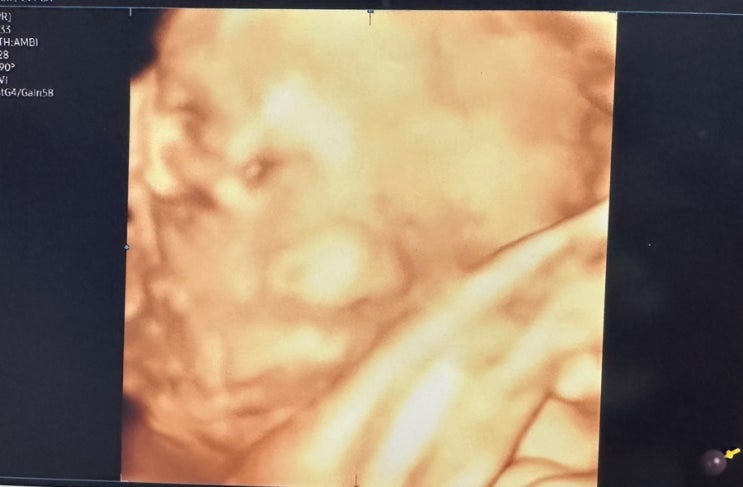

[37주차 기록] 분만전 마지막 진료, 제왕절개 준비, 삼성창원병원 분만

7월이 되면서 출산이 10일도 남지않았다는 사실에 설레는 마음 반 걱정되는 마음 반으로 마지막 진료를 보...